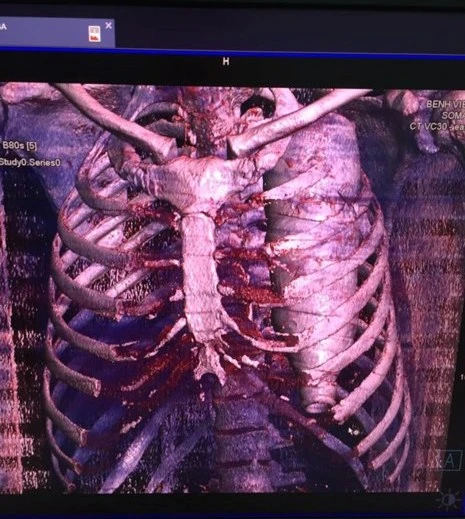

Hình ảnh trong lồng ngực ông B. Ảnh: AB

Đây là một trường hợp rất hi hữu. Ảnh: AB

Sau tai nạn, ông B. bị gãy hai xương sườn nhưng không có tổn thương nghiêm trọng nào khác. Sau khi hội chẩn, các bác sĩ đã tiến hành mổ cấp cứu để lấy vỏ chai ra khỏi lồng ngực ông B.